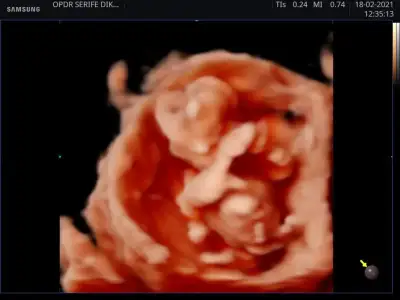

dr soylemeden siz gorun genital nub teorisi ( bebegin cinsiyeti)

Bana da bakarmısınız karından 12 +2 günlük ultrason

Acısı 30° canım belkide ileri haftada yükselir başka USG varsa paylaşın 11+4 USG erkekte olabilir 🤗13 haftada nubu tam net olur aslında 🙈 oranları ilk sayfaya yazmıştım